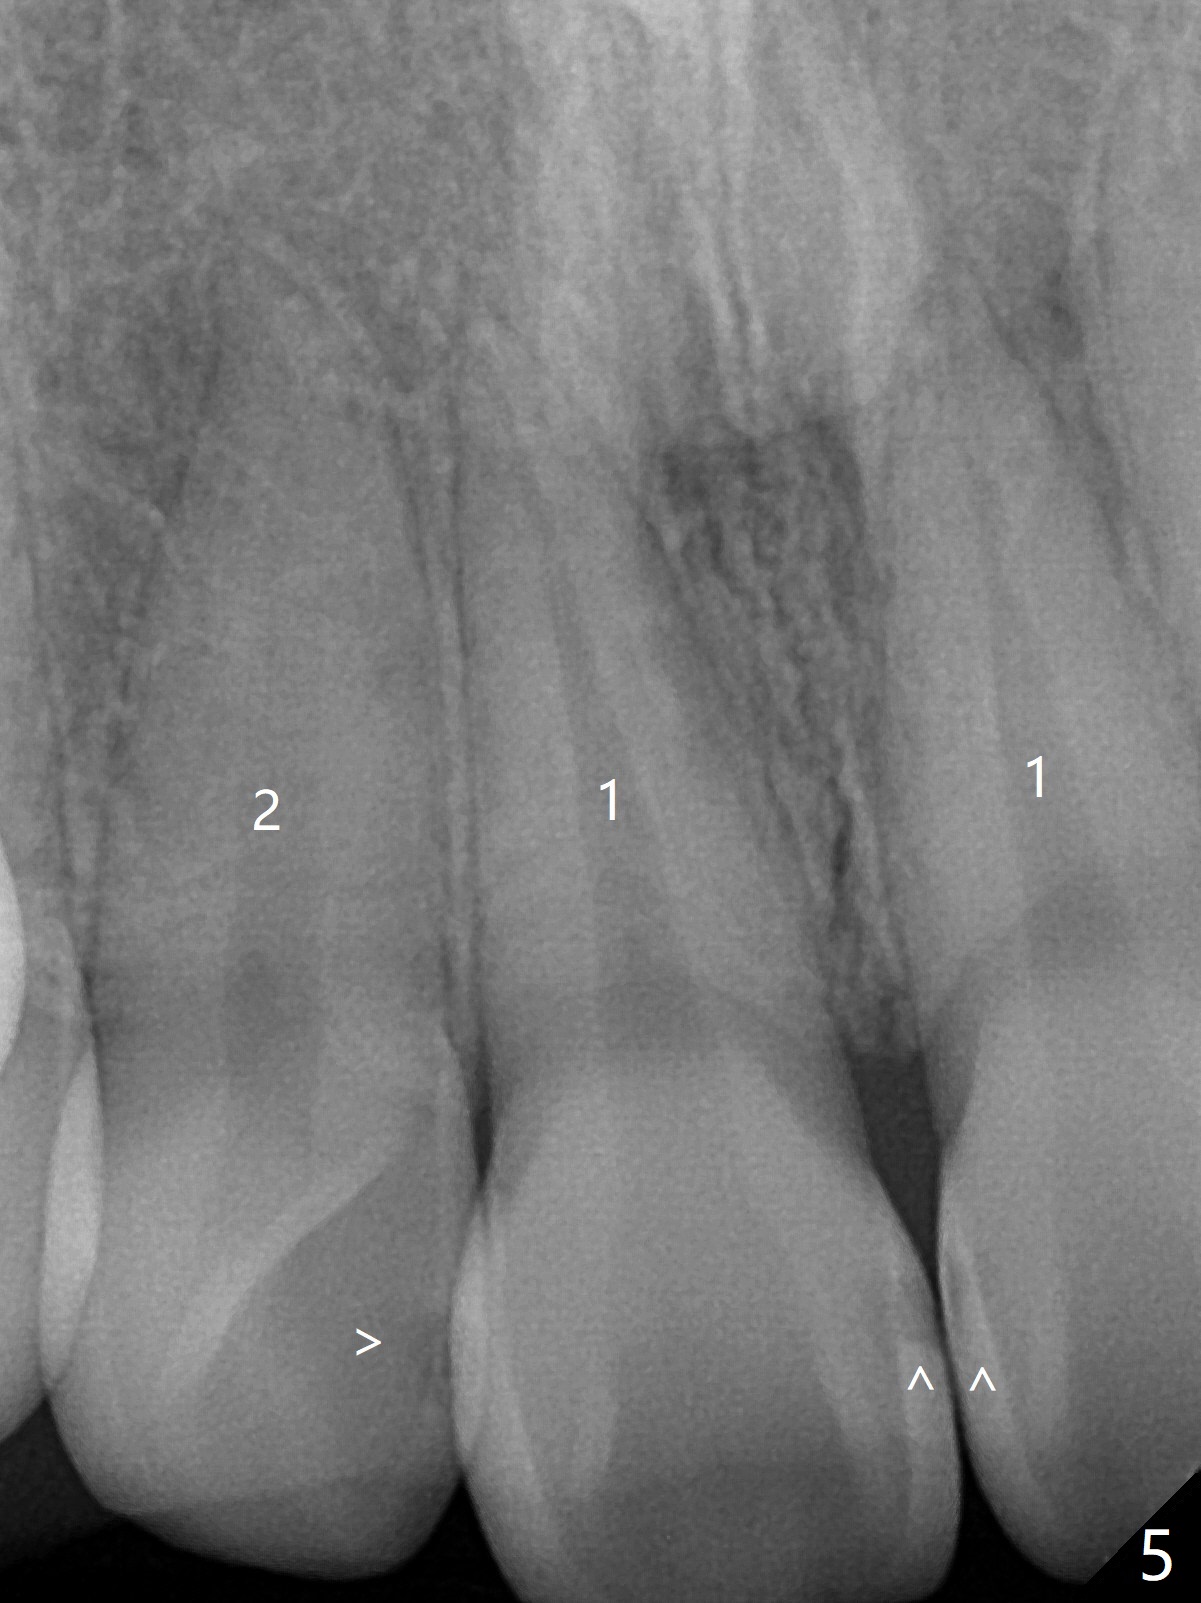

13岁女孩面型正常,先天性缺失右下1(图一,四,七),前牙深覆盖(图二),邻牙扭转(图三),治疗计划使用隐形矫正器,上牙片切,内收,关闭下切牙间隙(图八)。片切前发现上切牙邻面龋(图五,六),最大一个已经修补(右上2),不知其余小的龋坏能否片切,涂氟保守处理?不过她有龋坏易感性,以前乳牙龋坏。邻面片切后,上,下颌分别用无色和蓝色树脂做attachments(图九)。不明白的是Reciprocating saw远不如wheel利索。